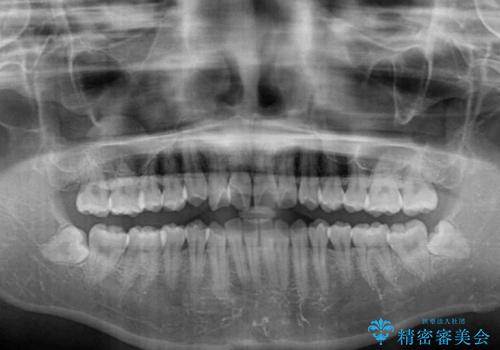

- 上下のデコボコと前歯のクロスバイトを改善したいとのことで来院された患者様です。

極力短期間で治療したいとのことで、ワイヤー装置による矯正治療を行うこととしました。